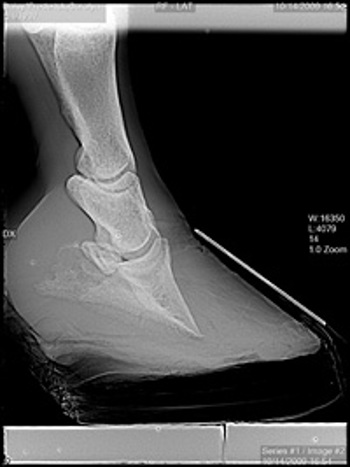

Our digital radiograph unit allows us to instantly see a high-quality image patient-side. This image can be adjusted to pick up even the most minor orthopedic changes. Images are stored electronically and copies on CD are available to you as well.

hock xray